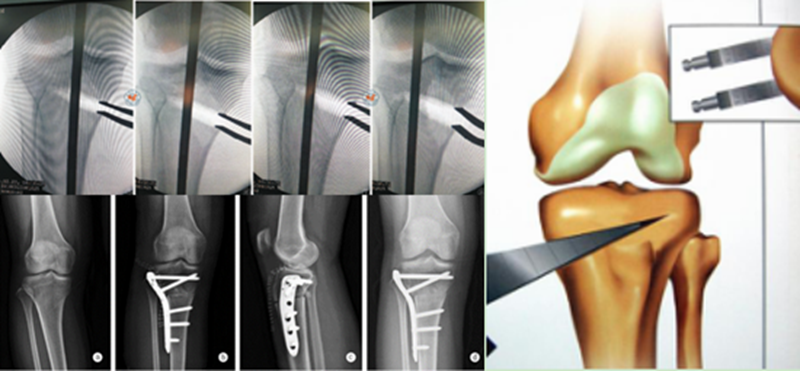

内侧开放楔形截骨(OWHTO)

OWHTO为胫骨近端内侧楔形截骨,逐渐撑开截骨端,改善力线。

优点:

可以更精确矫正下肢力线,矫正角度相对较大;

无需进行腓骨截骨,并且保留了外侧约1cm的骨性合页;

允许早期下地,康复快速。

缺点:

截骨端愈合时间长,骨缝过大需要植骨,不愈合率较高。

Coventry建议内翻畸形至少矫正至股骨胫骨解剖外翻角8°;Hernigou等发现患者术后机械外翻角在3°-6°时临床效果较好;Fujisawa等发现如果HTO术后力线通过胫骨外侧平台的30%-40%,软骨破坏则不再进展,若通过胫骨平台外侧的62%,则为最佳点,此点被定义为Fujisawa点。

A.双平面截骨,第一刀沿水平面在胫骨后2/3进行截骨,保留外侧合页约10mm,第二刀沿冠状面在胫骨前1/3进行截骨,两刀截骨角度呈110°。B.撑开器逐渐缓慢加大骨缝,注意保留外侧合页。C.力线杆定位,撑开至力线杆经过Fujisawa点。D.进行内固定。